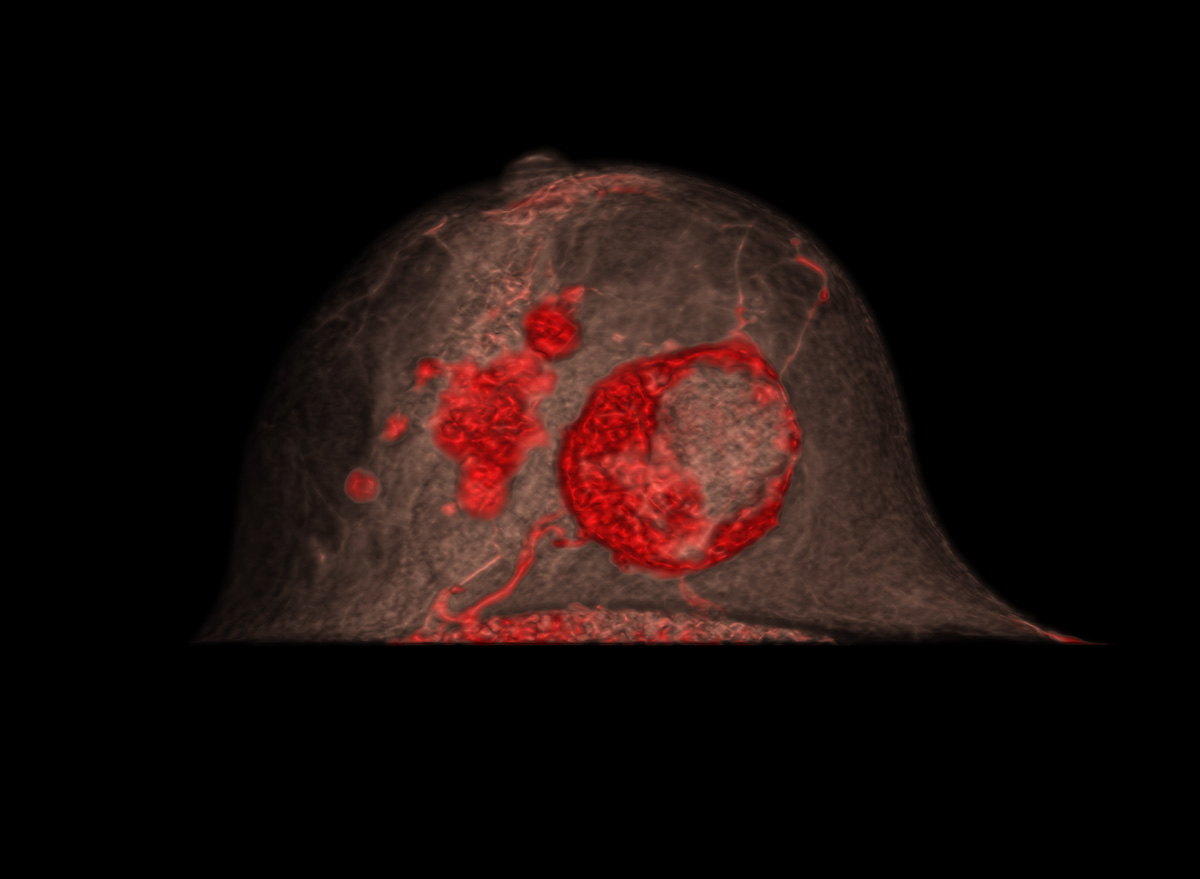

为了证实有多中心乳腺癌,她接受了乳腺 CT 扫描。

评估: BI-RADS 5

图片由 Prof. Dr. med. Evelyn Wenkel (埃尔兰根大学医院)